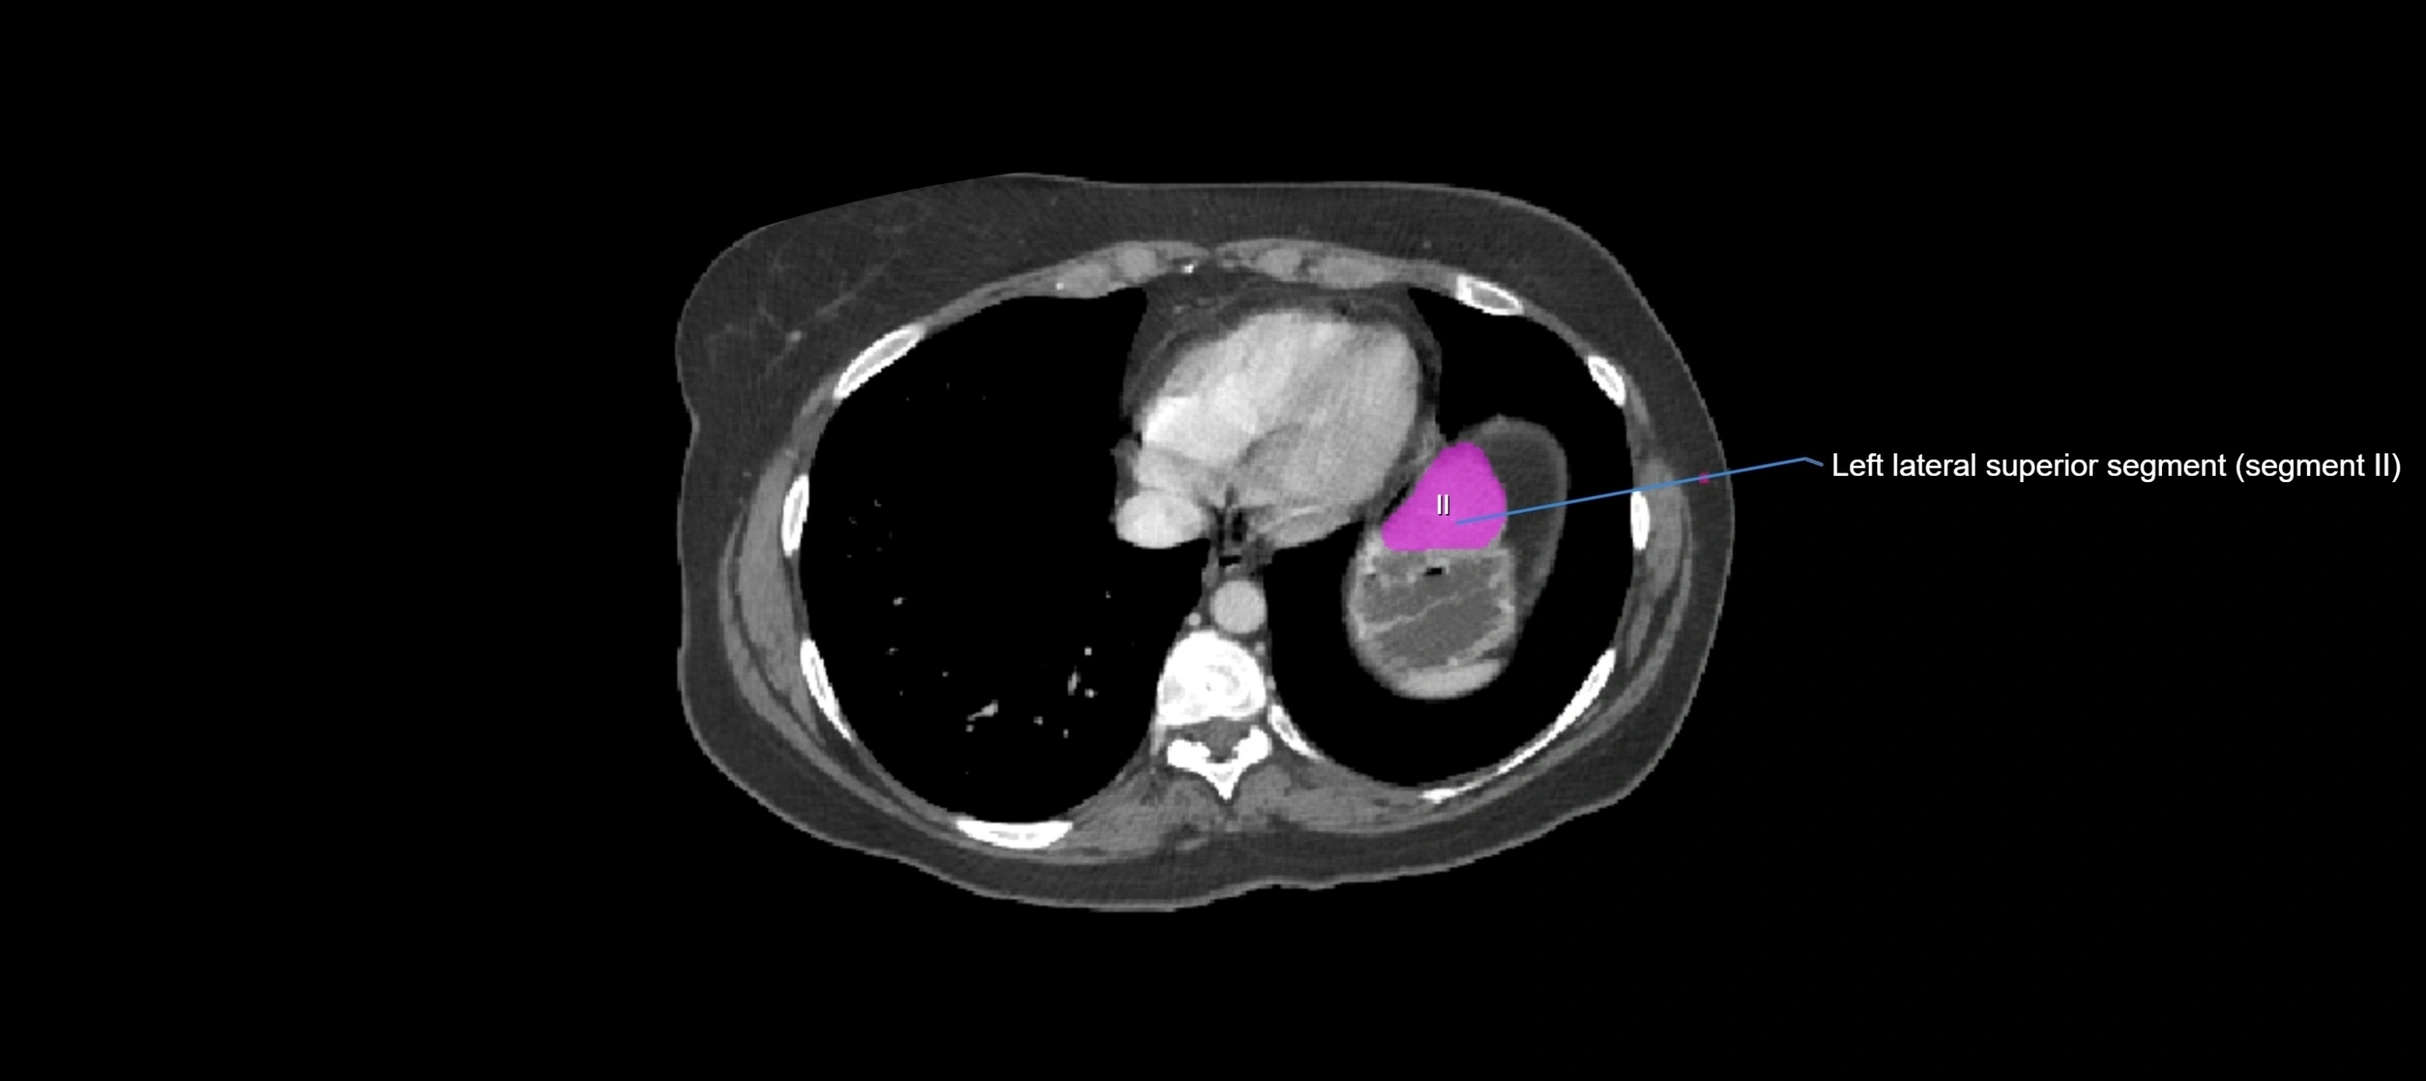

MRI image

image